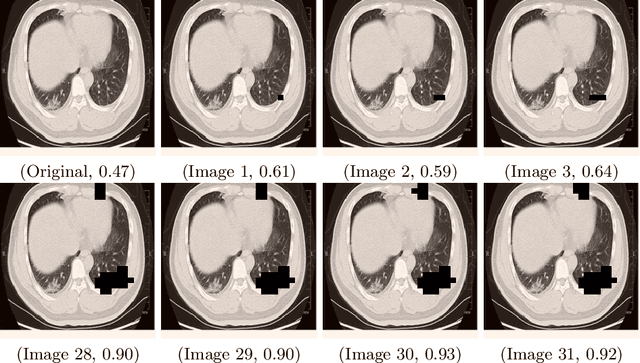

Abstract:Radiologist examination of chest CT is an effective way for screening COVID-19 cases. In this work, we overcome three challenges in the automation of this process: (i) the limited number of supervised positive cases, (ii) the lack of region-based supervision, and (iii) the variability across acquisition sites. These challenges are met by incorporating a recent augmentation solution called SnapMix, by a new patch embedding technique, and by performing a test-time stability analysis. The three techniques are complementary and are all based on utilizing the heatmaps produced by the Class Activation Mapping (CAM) explainability method. Compared to the current state of the art, we obtain an increase of five percent in the F1 score on a site with a relatively high number of cases, and a gap twice as large for a site with much fewer training images.